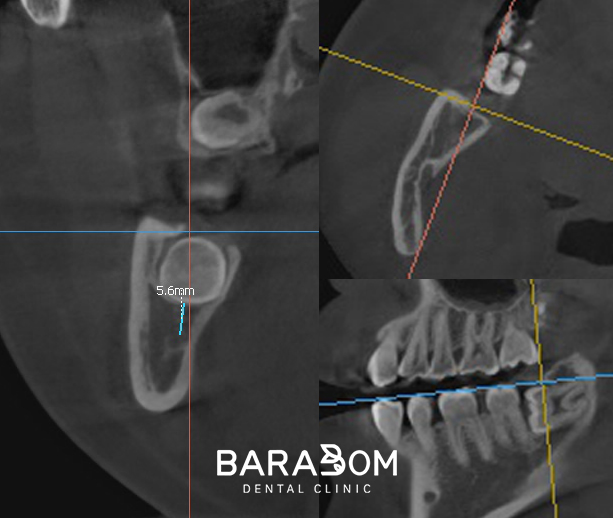

3D-CT 촬영을 통해 신경관의 위치를

입체적으로 분석하는 과정이 필요하죠.

CT 판독 시 확인하는 내용은

신경관과 치근의 거리,

신경관의 주행 방향,

치아 분할 시 안전 영역 등입니다.

따라서, 3D-CT를 이용하여

각 부위별로 신경관과의 위치와

치근의 거리를 체크하여

진료 계획을 수립해야 됩니다.

하치조신경이 치아 하방 3mm 지점에 위치한다면

치아를 분할할 때 절삭 기구가

그 이상 내려가지 않도록 계획을 세웁니다.